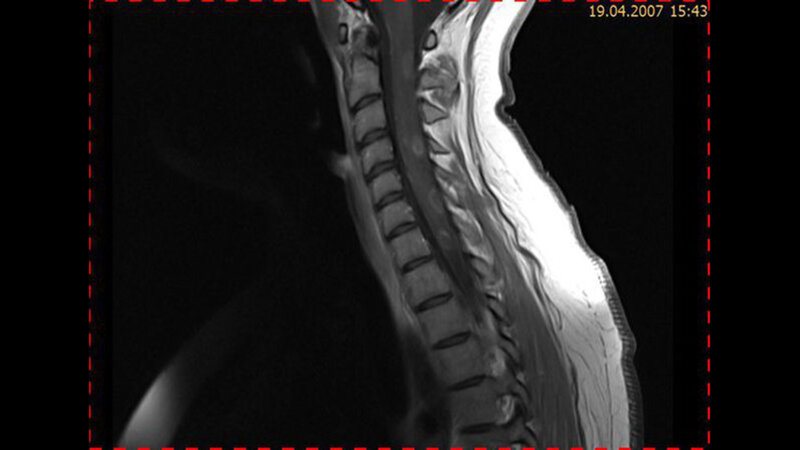

Entzündliche Veränderungen: postmyelitische Gliosen

Entzündliche Veränderungen der Wirbelsäule können das Rückenmark, die Bandscheiben, Gelenke, Wirbel und die paravertebrale Muskulatur betreffen.

Die Symptome der Myelopathie sind verschieden und unspezifisch. Die Myelitis kann Parästhesien, zunehmende sensomotorische Defizite sowie Darm- und Blasenstörungen verursachen. Die MRT ist eine bedeutende Methode in der Diagnostik der Myelopathie. Die Myelitiden sprechen gut auf eine immunsuppressive Therapie an.